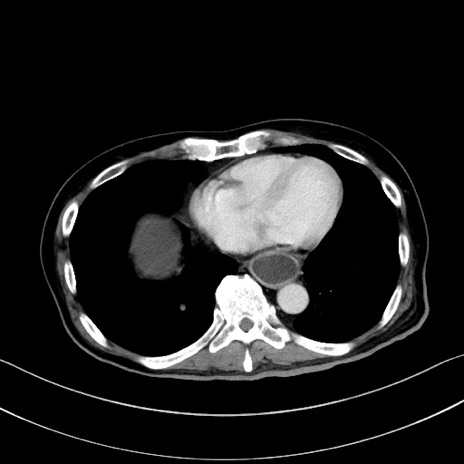

症例28(横断像)

【症例】60歳代男性

【主訴】嘔吐

【現病歴】胃癌にて胃全摘後。食思不振が悪化し、夜中に嘔吐することがある。

【既往歴】胃癌、胃全摘、脾摘、胆摘後

【データ】WBC 5900、CRP 10.56